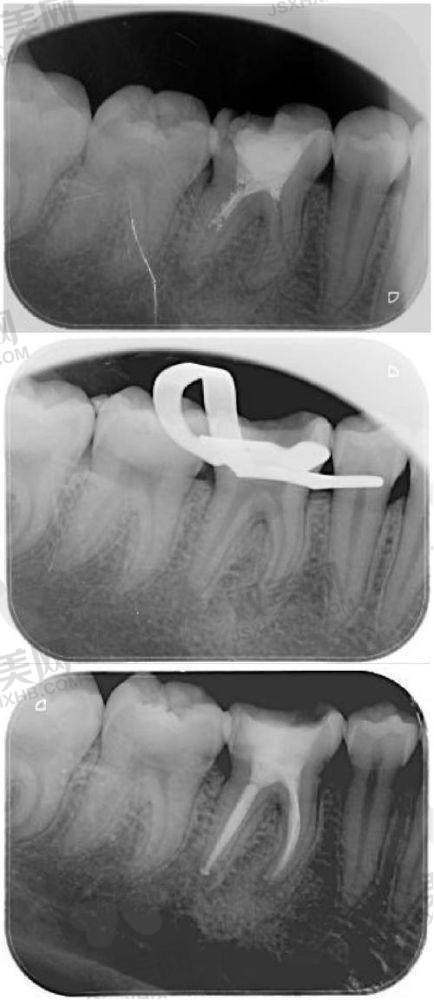

张琪医生的拿手好戏可不少。在正畸方面,她有着丰富的经验和不错的技术,能够根据患者的不同牙齿情况,制定出个性化的正畸方案。无论是牙齿排列不齐、龅牙还是地包天等问题,她都能轻松解决,让患者拥有整齐美观的牙齿。在牙周疾病治疗领域,她更是有着深厚的知识储备和丰富的临床经验。她可以正确地诊断各种牙周疾病,并为患者提供有效的治疗方案,改善患者的口腔健康功能。另外,在口腔修复方面,张琪医生也有着特别高的造诣,能够为患者打造出合适的修复体,修复牙齿的正常功能和美观。

张琪医生的技术特点可以用“精细、专精、个性化”来概括。在诊断过程中,她就像一位侦探,能够精细地找出患者口腔问题的根源。在治疗方案的制定上,她会充分考虑患者的年龄、牙齿状况、个人需求等因素,为每一位患者量身定制更适合的治疗方案。在治疗过程中,她操作熟练、手法轻柔,尽量减少患者的痛苦。同时,她还会不断关注治疗成效,根据患者的反馈及时调整治疗方案,确保治疗达到至佳成效。